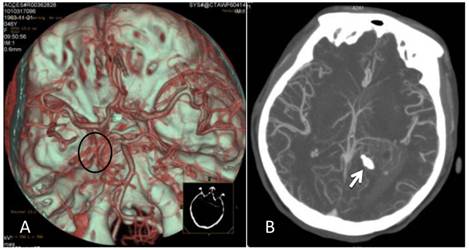

After controlling arterial blood supply, the surgery was successful, and the tumor was completely removed. Postoperatively, the patient recovered well. However, at day 7 the patient became depressed and then entered a confused state of mind. Physical examination revealed a dilated left pupil (4.5 mm in diameter), lack of a pupillary light reflex, and a paralyzed right limb accompanied by pathological reflex. Head CT showed severe edema surrounding the surgical field. The ipsilateral ventricle was compressed and deformed and the midline had shifted to the opposite side, which was considered to be brain herniation caused by cerebral edema. Emergency treatment with decompression via bone removal was performed (Figure 4). Postoperatively, the patient recovered well but developed left homonymous hemianopia. The patient was in a good state at the 6-month follow-up, but the hemianopia did not resolve.

Figure 4

Postoperative CT. A: Re-examination at day 7 post operation showed that the tumor had been removed but that severe edema surrounded the lesion and the midline had shifted to the opposite side. B: After decompression, there was still edema surrounding the trigone of the lateral ventricle, but the midline was located in the middle.

For the meningiomas of the trigone of lateral ventricle, there are several approaches used, such as superior parietal lobe approach and parieto-occipital approach [22]. In our case, we chose the temporoparietal approach instead of other approaches, because as shown by the CTA image, the lesion was supplied by anterior and posterior choroidal arteries, and maximum intensity projection clearly revealed a high-density calcification shadow at the rear of the lesion. It was convenient to control the arterial blood supply using the temporoparietal approach. The surgery was successful, and the tumor was completely removed after the control of arterial blood supply. However, at day 7 the patient became depressed and entered a confused state of mind. CT showed brain herniation due to the occurrence of cerebral edema. The mechanism of postoperative edema surrounding the surgical field in this case is different from the edema surrounding meningioma, which is associated with venous compression, tumor-related pressure, arterial blood supply and secretion of angiogenic factors such as vascular endothelial growth factor [23]. In this case the postoperative edema surrounding the surgical field mainly resulted from surgical trauma after tumor removal.